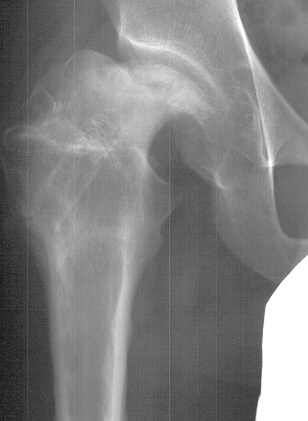

- Post Operative Day 18: R hip Xray: subluxation of R hip, possible metaphyseal

lucency consistent with osteomyelitis. Taken to OR for repeat I & D

Institute. Initial labs: WBC 15,100, ESR 72. R hip Xray: changes in proximal

. metaphysis including lucency and demineralization, hip subluxated. Treated

with oxacillin and Pavlik harness.

- 2 month Office Follow Up: Rt hip Xray: progressive destruction of capital

femoral epiphysis, cystic changes in metaphysis consistent with AVN.